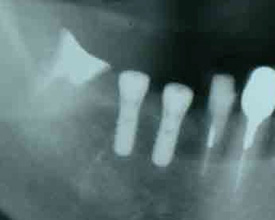

インプラント植立直後のレントゲン

[20] インプラント植立直後のレントゲン高ヒット